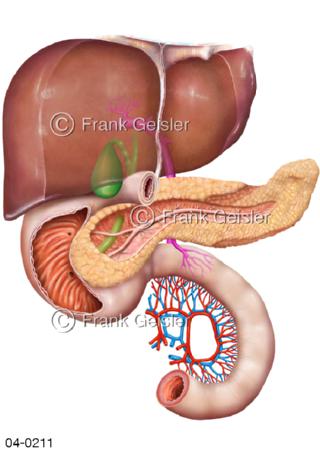

Bildergalerie Topografie Organe

Bilder zur topografischen Anatomie, die Lage der Organe und die Strukturen nach ihren räumlichen Lagebeziehungen zueinander, Übersicht der inneren Organe im Kopf und im Rumpf, Topografie der Organe im Brustraum (Thorax) und im Bauchraum (Abdomen)